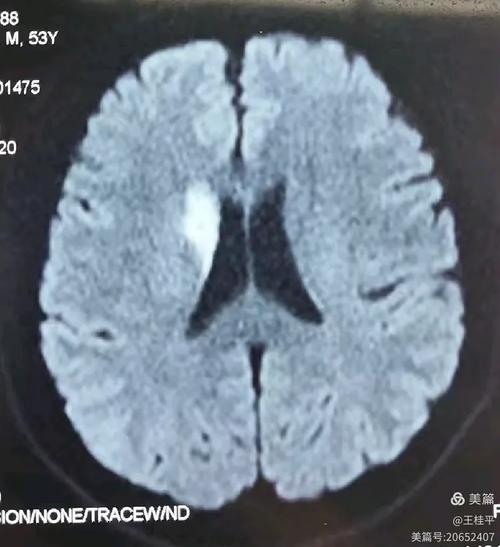

大面积:这是最关键、也是最严重的一点,它意味着堵塞的血管主干非常粗大,导致其供应的整个脑叶(如整个额叶、颞叶、顶叶,或它们的组合)都发生了梗塞,梗死的脑组织范围很广,通常梗塞体积会超过50-80毫升,甚至更多。

- 偏瘫:左侧身体完全瘫痪,无法活动,这是最核心的症状之一。

- 偏身感觉障碍:左侧身体对疼痛、温度、触觉等感觉完全丧失或减退。

- 偏盲:左侧视野缺损,即双眼向右看时,左侧一半的世界是“黑”的。